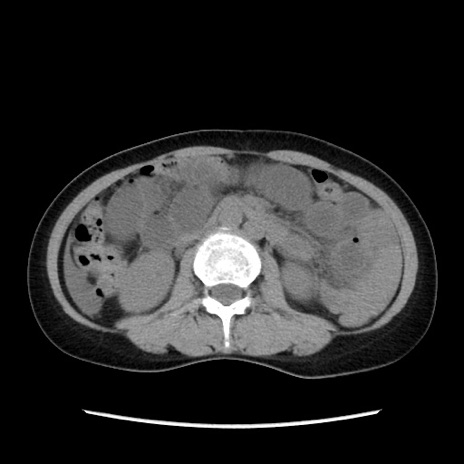

症例32(横断像)

【症例】40歳代 女性

【主訴】上腹部痛、嘔気・嘔吐

【現病歴】約9時間前頃から急に上腹部痛、嘔気、嘔吐が出現。改善しないため救急要請。

【既往歴】子宮頚癌(広汎子宮全摘術、放射線療法)、腸閉塞

【身体所見】腹部:平坦、軟、腸雑音亢進、上腹部を中心に腹部全体に圧痛あり。

【データ】WBC 8400、CRP 0.03